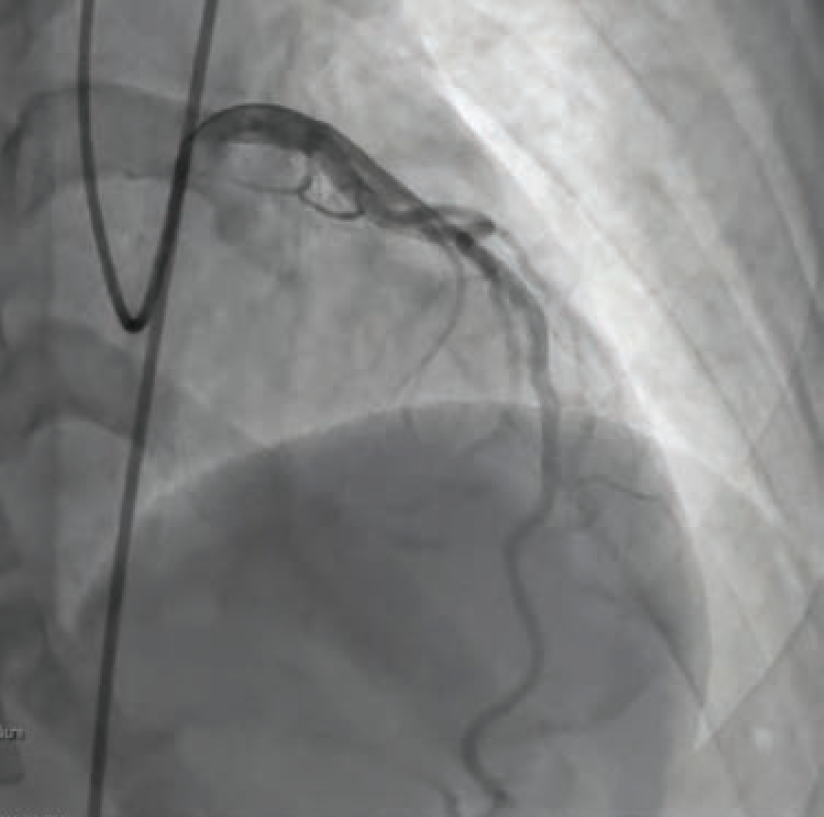

A 68-year-old male with a past medical history significant for hypertension, hyperlipidemia, coronary artery disease status post percutaneous coronary intervention (PCI) of the proximal to distal right coronary artery (RCA) 5 years prior to presentation arrived in the Emergency Department (ED) at MedStar Southern Maryland Hospital Center by Emergency Medical Services as a Code Heart, with concerns for an inferior ST-elevation myocardial infarction (STEMI). The patient reported that he was physically exerting himself at home when he suddenly started to experience crushing, substernal, and left-sided chest pain with associated lightheadedness, shortness of breath, and nausea. In the ED, patient was hypotensive and in complete heart block (CHB). The patient was evaluated by interventional cardiologist Dr. Brian Case in the ED and within 10 minutes of arrival, the patient was emergently taken to the cath lab.

Once in the cath lab, the team of nurses and technologists worked swiftly alongside Dr. Case to first establish safe femoral access (ultrasound guidance and micropuncture technique) given the patient’s hemodynamic instability. Next, while promptly inserting a temporary venous pacemaker to address the patient’s complete heart block, the first episode of ventricular fibrillation occurred, and the first shock was successfully delivered. The team then placed an intra-aortic balloon pump (IABP) for cardiogenic shock management in the setting of right ventricular (RV) infarct. The operator used a 5 Fr Judkins left (JL)4 catheter to perform left coronary angiography and a 6 French hockey stick guide catheter for right coronary angiography. The patient was noted to have instent thrombosis (Figure 1), requiring mechanical aspiration thrombectomy (Penumbra). During the intervention, the patient experienced recurrent ventricular fibrillation. The cath lab team worked in unison to successfully deliver 19 shocks throughout the procedure, while administering several intravenous medications, including amiodarone, lidocaine, magnesium, bicarb, and Levophed (norepinephrine bitartrate), per the operator’s orders. Despite the critical arrhythmias and several interventions required to stabilize the patient, the team achieved a remarkable 49-minute door to balloon time in this case.